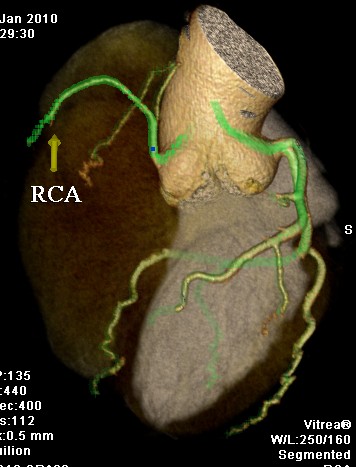

标题: CT24400:患者54岁,心前区不适进行心脏冠脉造影检查。 [打印本页]

标题: CT24400:患者54岁,心前区不适进行心脏冠脉造影检查。

患者54岁,心前区不适进行心脏冠脉造影检查。高手看看有问题没有?

图像很漂亮,好像未见异常